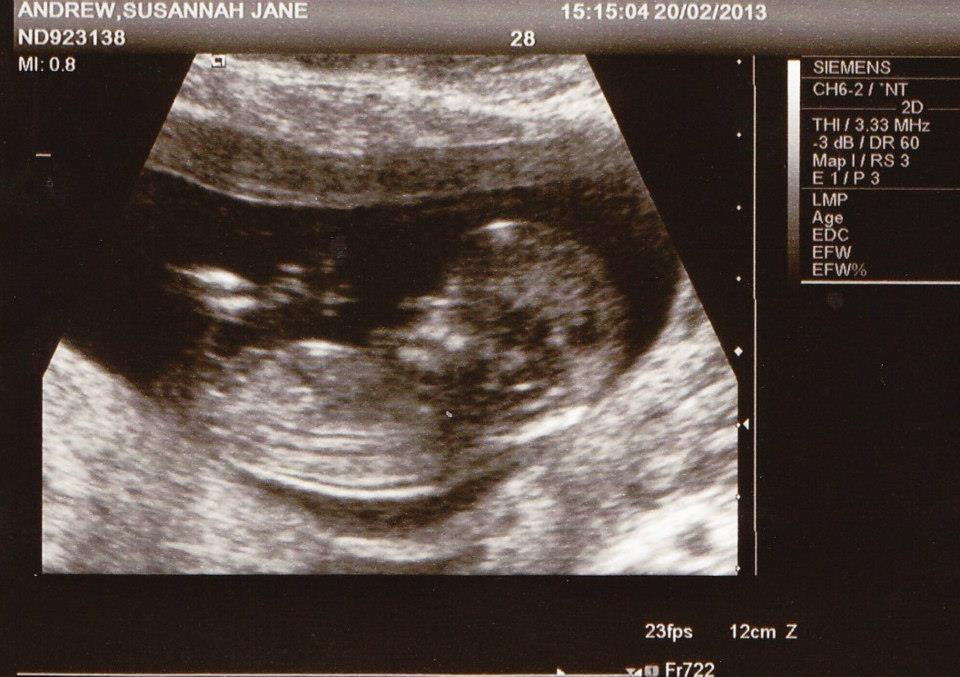

These are for a friend. They were both taken on the same day at 12 weeks 5 days. Is there a nub visible? Would appreciate any guesses.

Attachment 9107